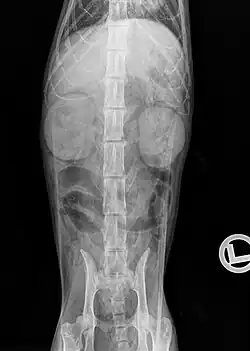

Urographie: Diffuse Anreicherung des Kontrastmittels in den Nieren bei einer Katze mit hochgradiger CNE.

Mit einer Röntgenuntersuchung lassen sich Größen-, Dichte- und Lageveränderungen der Nieren sowie einige Harnsteine (Struvit- und Calciumoxalatsteine sind „röntgendicht“) und Weichteilverkalkungen nachweisen. Bei stark abgemagerten Katzen oder Flüssigkeitsansammlungen im Retroperitonealraum ist die Niere im Röntgenbild jedoch aufgrund der daraus resultierenden Kontrastminderung nur bedingt darstellbar. Eine höhere diagnostische Aussage hat die Ausscheidungsurographie, bei der ein röntgendichtes Kontrastmittel (z. B. Iopamidol, Iohexol) in die Blutbahn gespritzt und dessen Ausscheidung über die Nieren röntgenologisch erfasst wird. Damit lassen sich Durchblutungsstörungen, Funktionsstörungen der Nierenkörperchen und Verlegungen der Abflusswege nachweisen.[22]